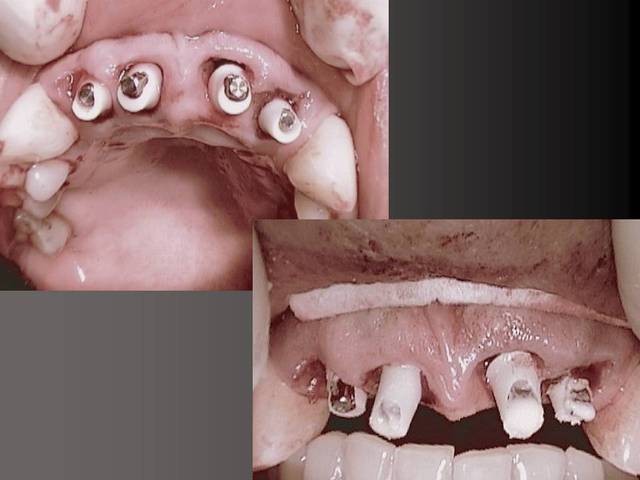

En dessous il y a des photos, dans une on voit (troisième) qu il n y a pas de resorption de l´os après 14 ans, ce que l´on voit c´est l´os très fin condensé sur l´implant.

Le premier photo c´est une erreur parce que le périoste est blessé et les foret "trop" grands.

Oui sans condenser juste en flapless ca serai moins évident. Pour moi-même en condensant j´ai besoin de 1 mm buccal minimum(plus il y a mieux c´est) mais dans ma pratique et celles mes confrères ca fonctionne et cela dure dans le temps depuis 16 ans.